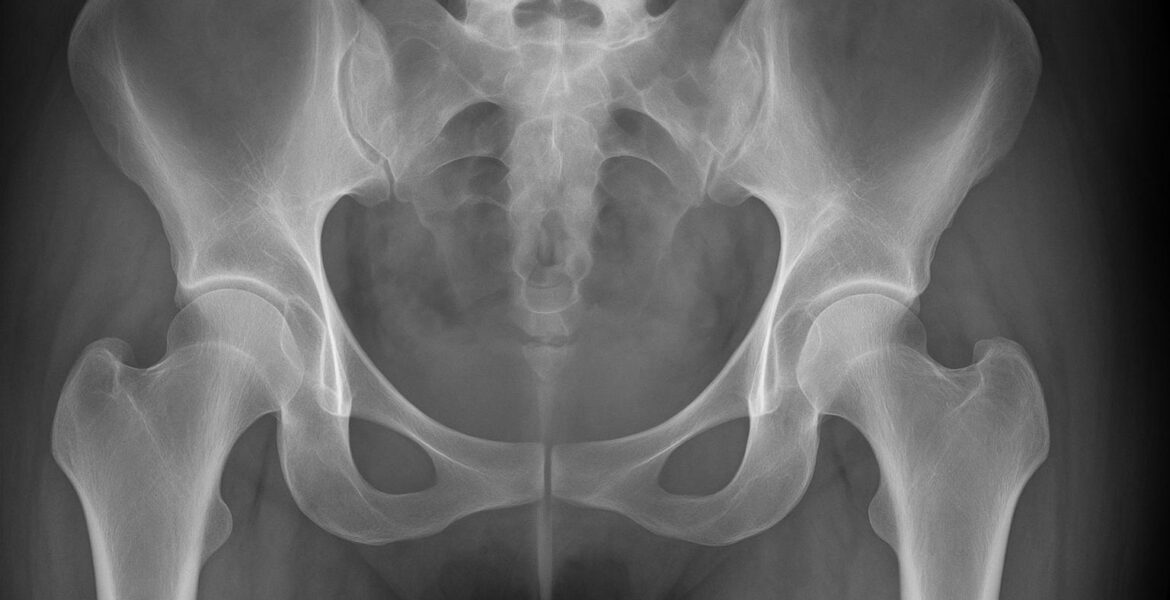

María Pérez: El suelo pélvico, también conocido como periné, es un conjunto de estructuras y tejidos que cierra la pelvis por abajo.

Para ubicarlo, basta con sentarte y buscar los huesos del culo sobre los que solemos apoyar el peso. Si trazamos una línea imaginaria desde ahí hasta el pubis y el coxis, formamos un rombo; dentro de esos cuatro puntos está el conjunto de músculos y fascias que lo conforman.

Este “sistema pélvico” no trabaja solo: se alía con el abdomen, las caderas y el diafragma para encargarse de cosas como: